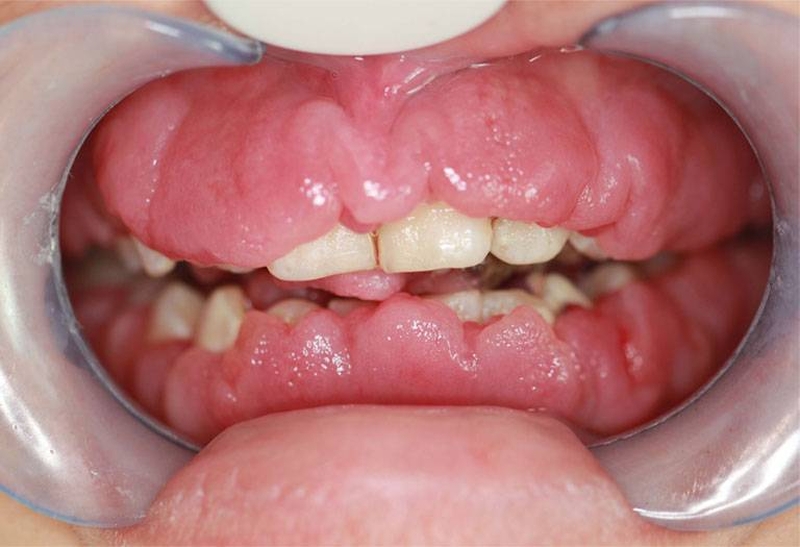

Viêm lợi phì đại là một biến chứng của bệnh viêm lợiViêm lợi phì đại là một biến chứng của bệnh viêm lợi, với biểu hiện đặc trưng là các mô nướu răng phát triển lớn bất thường bao phủ thân răng. Khởi phát bệnh là do chứng viêm lợi thường gặp, nhưng không phải ai bị viêm lợi cũng sẽ bị phì đại. Đây có thể là hệ quả do giai người bệnh chủ quan không điều trị viêm lợi dứt điểm và đúng cách. Từ đó dẫn đến hậu quả bệnh tái phát liên tục với những biểu hiện nặng, lâu dần chuyển sang phì đại lúc nào không hay.

Những biểu hiện của bệnh viêm lợi phì đại:

U xơ nướu hay còn gọi là tăng sản nướu di truyền là một loại viêm nướu hiếm gặp. Chúng bắt đầu phát sinh khi răng sữa bắt đầu mọc, vì khi các răng vĩnh viễn mọc lên, chúng cũng phát triển theo và và gây viêm lợi phì đại. Chúng sẽ dần dần bao phủ toàn bộ thân răng, chỉ gây đau khó chịu cho đến khi mô phì đại bao phủ một phần của bề mặt răng.